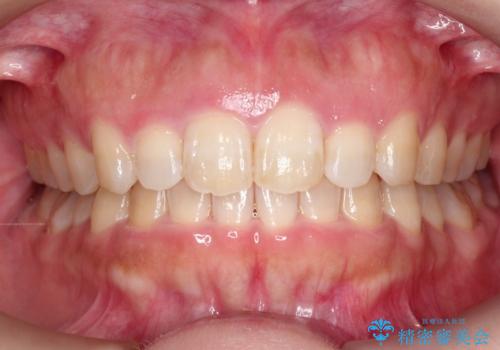

八重歯をインビザラインで非抜歯矯正